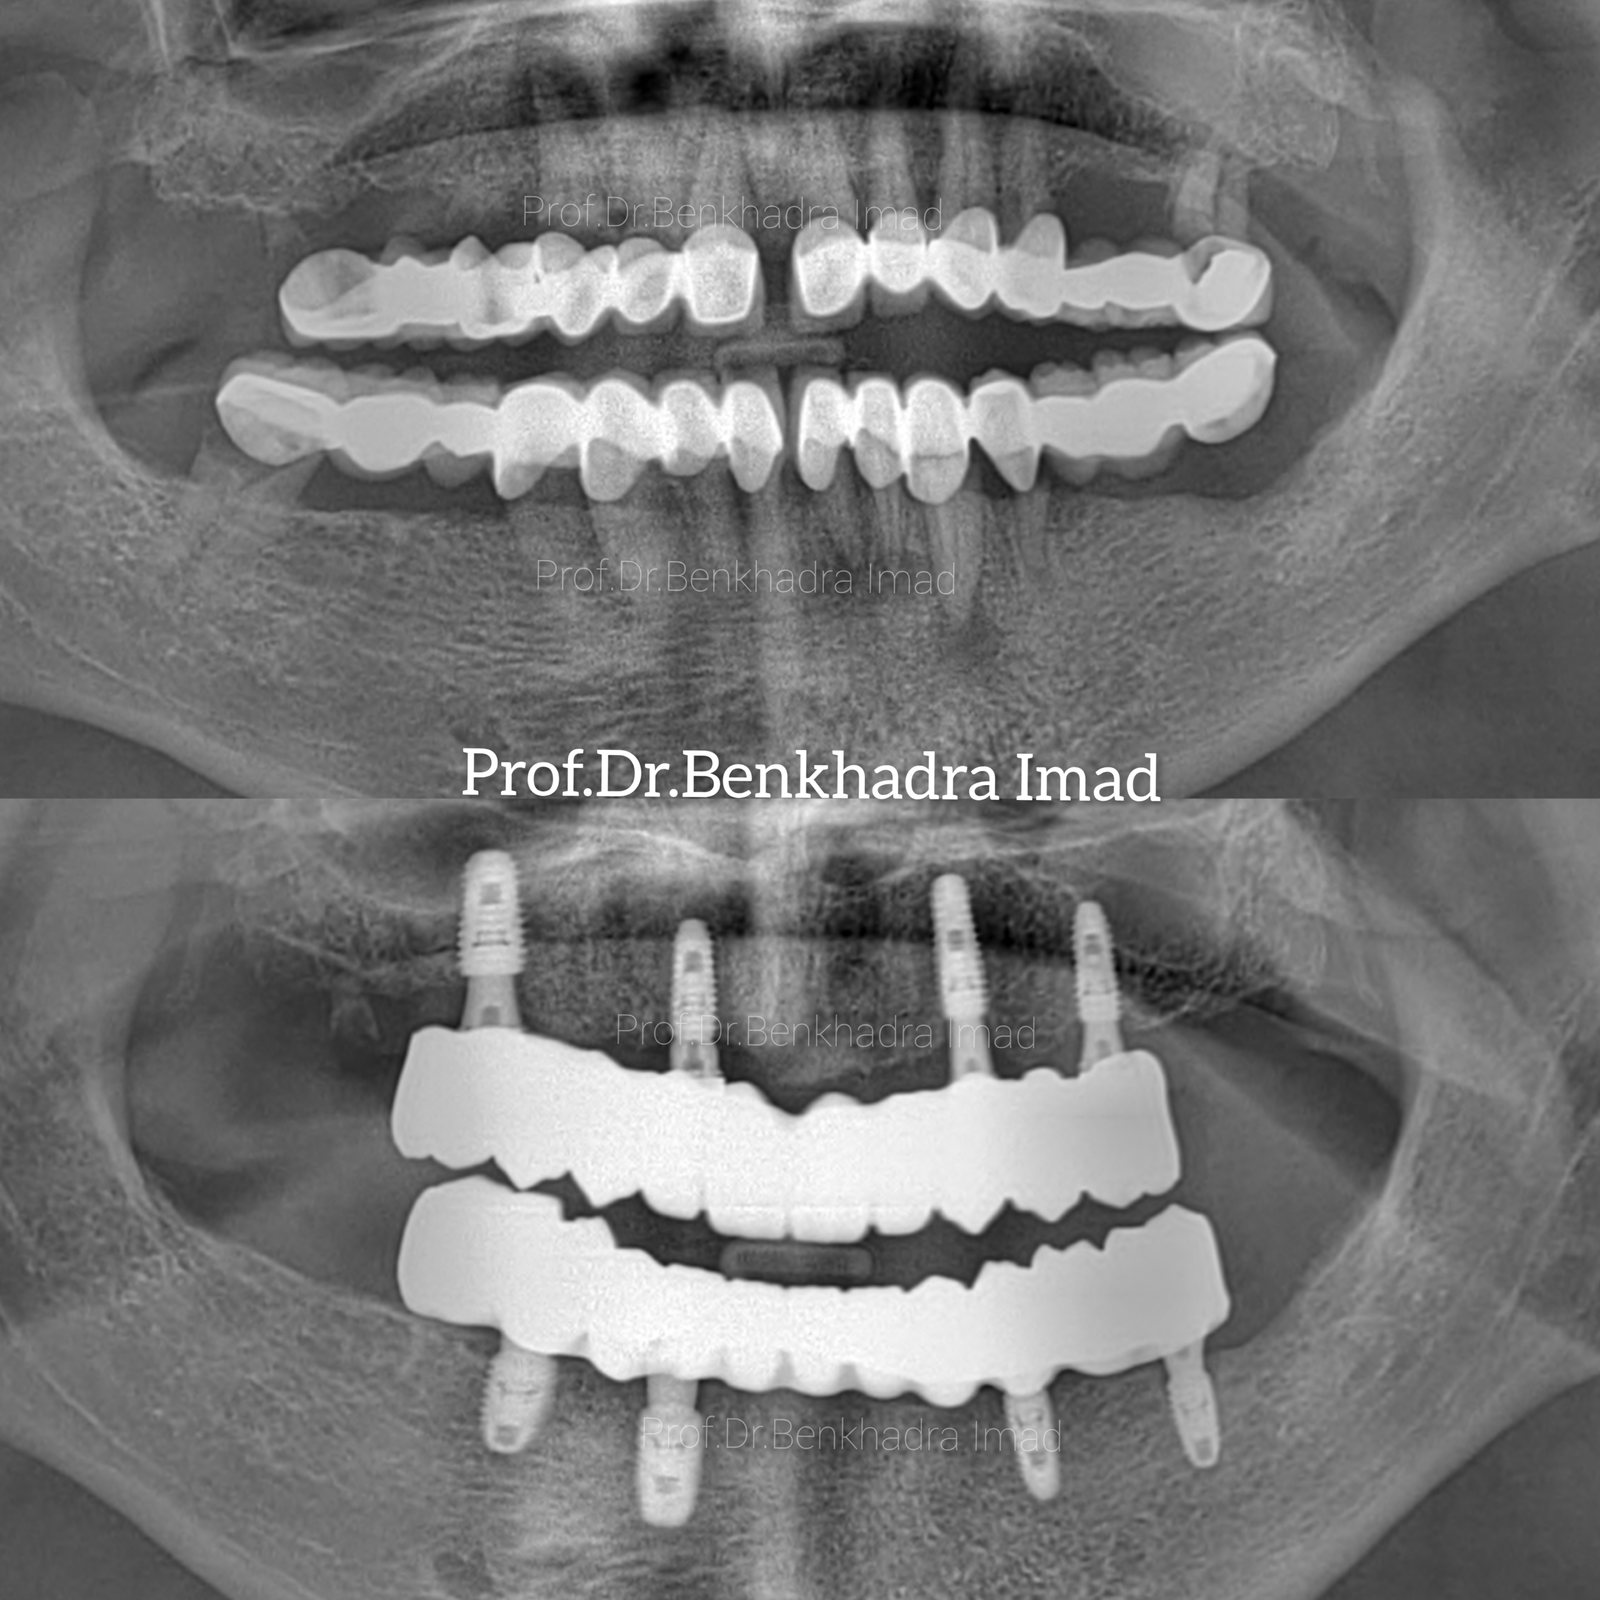

Full Smile Rehabilitation with Dental Implants | Real Case